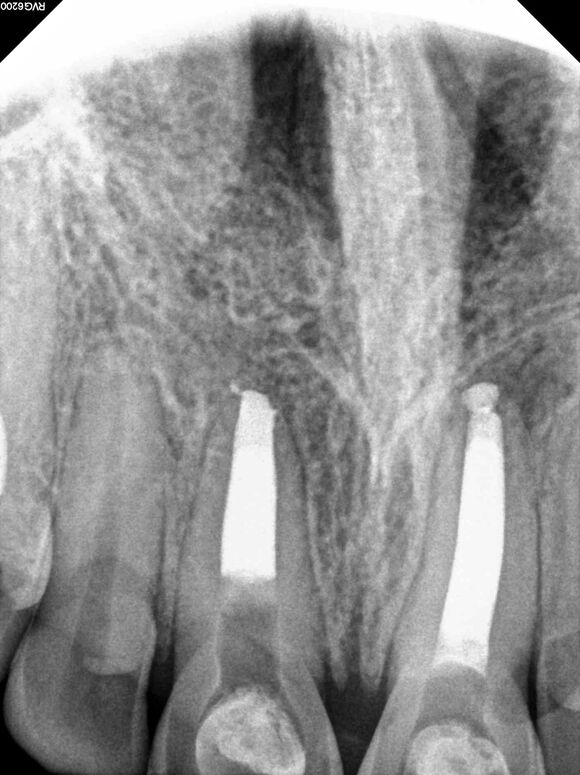

Beispiel 5: Vorher

Die seitliche Lage lässt weitere Wurzelkanäle vermuten.

Beispiel 5: Nachher

3 Wurzelkanäle bei diesem Zahn, sind zum Glück sehr selten!